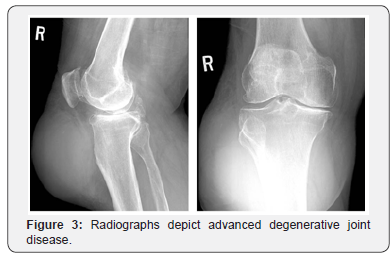

A 74yr male with a past medical history of osteoarthritis bilateral shoulders, coronary artery disease, congestive heart failure with cardiomyopathy, hypertension, peptic ulcer disease, gastric reflux, type 2 diabetes mellitus, gout and varicose veins presented with chronic right knee pain with associated subcutaneous bursa on his right leg that had been progressively increasing in size for 8-9 years (Figures 1-4). As the bursa could be decompressed entirely from an anterior midline incision, it was decided by the surgeon that the bursa would be removed at the same time as the total knee arthroplasty. The patient underwent excision of a massive subcutaneous bursa found over the anterolateral and posterolateral aspect of the leg (Figures 5-8) utilizing a midline incision, following which a total knee arthroplasty was performed using a medial parapatellar arthrotomy. The tourniquet was inflated during the procedure and was released before closure with a tourniquet time of 110 minutes. The wound was closed in layers over four 1/8th inch hemovac drains (2 placed in the joint and 2 placed in the bursal cavity).